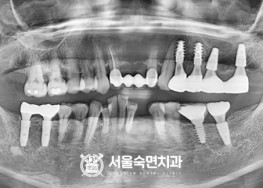

임플란트-치료-전후사진